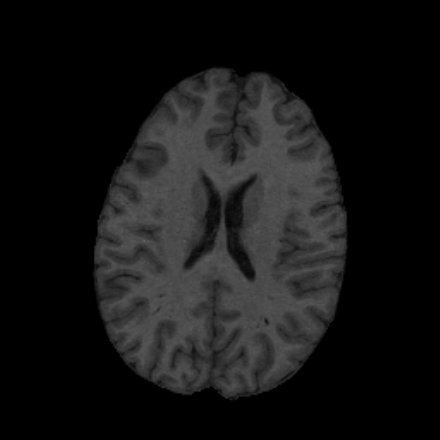

• use magnetic resonance (MR) images to display anatomical information (see Figure 1)

MR Scan from One Subject MR Scan from a Second Subject

Figure 1: MR image scans from two different subjects illustrate the variability in anatomical structure between individuals.